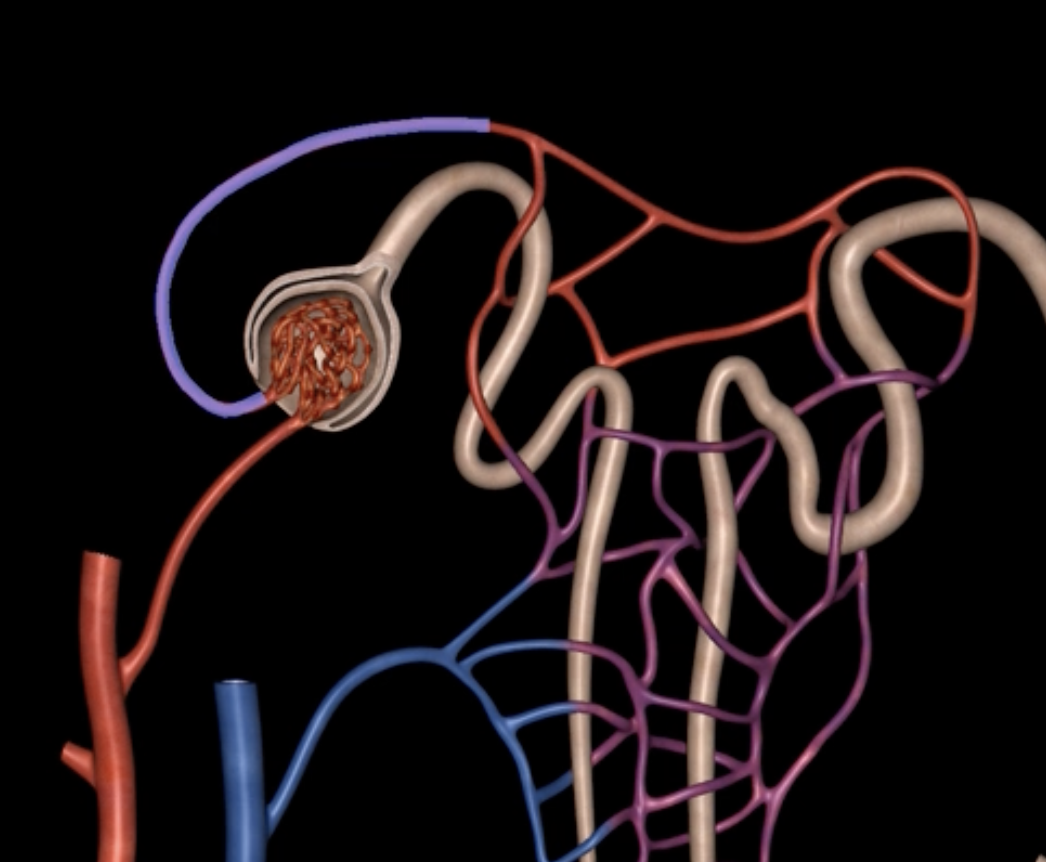

afferent arteriole

yellow

glomerulus

green

efferent arteriole

purple

orange: peritubular capillaries

green: vasa recta

efferent arteriole give rise to orange and green

yellow: cortical nephron

blue: juxtamedullary nephron

yellow:

blue: